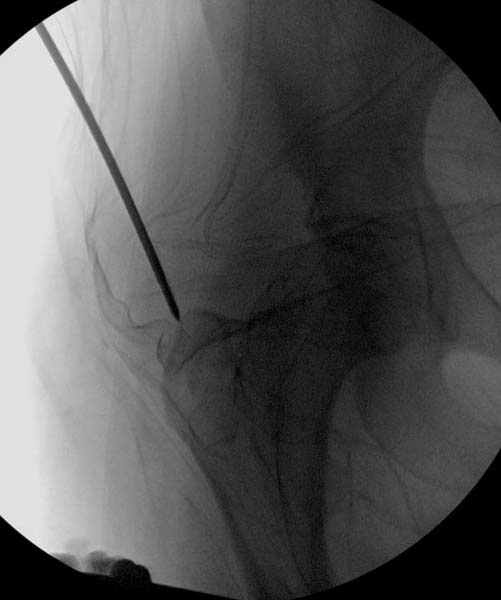

По характеру повреждения головка находится сзади и напрашивается задний Кохер-Лангенбек доступ, но в заднем доступе имеется риск повреждения магистрального кровоснабжения головки a. circumflexa. Более щадящая trochanteric flip (digastric osteotomy) сохранит кровоснабжение и дасть возможность работу при вывихнутом суставе.

Остеосинтез бедра не стали делать из-за множественных переломов ребер с ушибом грудной клетки и поэтом у закончили фиксацию бедра наружным фиксатором.